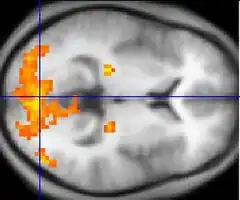

![]() Colour vision area shown as V8 on upper image | |

The colour centre is a region in the brain primarily responsible for visual perception and cortical processing of colour signals received by the eye, which ultimately results in colour vision. The colour centre in humans is thought to be located in the ventral occipital lobe as part of the visual system, in addition to other areas responsible for recognizing and processing specific visual stimuli, such as faces, words, and objects. Many functional magnetic resonance imaging (fMRI) studies in both humans and macaque monkeys have shown colour stimuli to activate multiple areas in the brain, including the fusiform gyrus and the lingual gyrus. These areas, as well as others identified as having a role in colour vision processing, are collectively labelled visual area 4 (V4). The exact mechanisms, location, and function of V4 are still being investigated.

Anatomical and physiological studies have established that the colour centre begins in V1 and sends signals to extrastriate areas V2 and V4 for further processing. V4 in particular is an area of interest because of the strength of the colour receptive fields in its neurons.[4] V4 was initially identified in macaque monkey visual cortex experiments. Originally, it was proposed that colour was selectively processed in V4. However, this hypothesis was later rejected in favour of another hypothesis which suggested that V4 and other areas around V4 work together to process colour in the form of multiple colour selective regions.[5] After identification of V4 as the colour-selective region in macaque monkeys, scientists began searching for a homologous structure in the human cortex. Using fMRI brain imaging, scientists found three main areas stimulated by colour: V1, an area in the ventral occipital lobe, specifically the lingual gyrus, which was designated as human V4, or hV4, and another area located anteriorly in the fusiform gyrus, designated as V4α.[4][6]